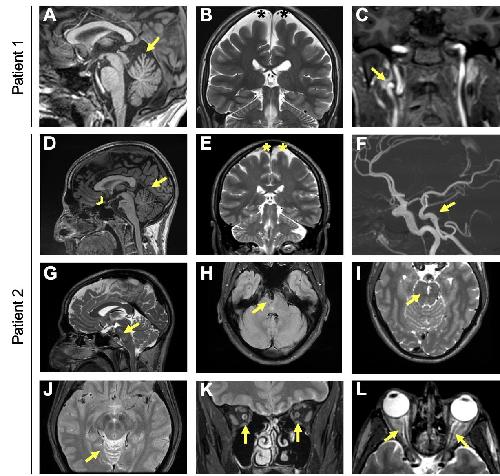

TBC1D32 variants disrupt retinal ciliogenesis and cause retinitis pigmentosa., Donval A,Masson C,Parain K,Kaminska K,Quinodoz M,Perea-Romero I,Garcia-Garcia G,Jimenez-Medina C,Boukhaddaoui H,Coget A,Leboucq N,Calzetti G,Gandolfi S,Percesepe A,Barili V,Uliana V,Delsante M,Bozzetti F,Scholl HP,Corton M,Ayuso C,Millan JM,Rivolta C,Meunier I,Perron M,Kalatzis V,Bocquet B,Borday C,Erkilic N,Mamaeva D, JCI Insight. November 8, 2023; 8(21):2379-3708.